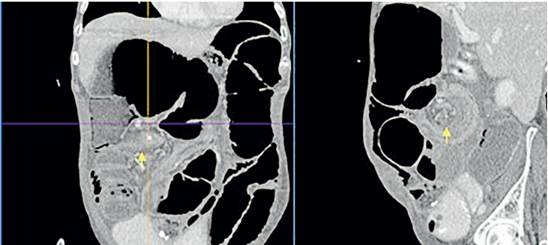

En la TC de abdomen (Figura 4) los hallazgos eran sugestivos de un vólvulo del ciego con obstrucción intestinal secundaria. Se realizó laparotomía exploratoria y se confirmó el diagnóstico (Figura 5), con hallazgos de ciego crítico dado por dilatación de hasta 15 cm de diámetro, dilatación del colon ascendente, transverso y de asas de intestino delgado, con cambios macroscópicos sugestivos de cambios crónicos por el compromiso gastrointestinal de su enfermedad de base.

Se realizó colectomía total e ileostomía terminal, pero en el posoperatorio nuevamente presentó íleo, que resolvió a los siete días. Con el inicio de la dieta tuvo producción elevada por la ileostomía, con un gasto entre 2000 y 2500 cc al día (en una paciente que pesaba 39 kg). Se dio manejo antisecretor con inhibidor de bomba de protones y loperamida a dosis máxima, sin lograr el control del gasto, por lo que se consideró falla intestinal tipo I y se inició nutrición parenteral total. Se hizo repleción nutricional durante 14 días, sin adecuada respuesta, por lo que se decidió realizar cierre de la ileostomía mediante anastomosis íleo-rectal durante la misma hospitalización. El gasto disminuyó a 500-700 cc al día y se dio egreso hospitalario. Durante el seguimiento, la paciente persistió con deterioro del estado nutricional, alto gasto fecal y falleció a los cuatro meses.